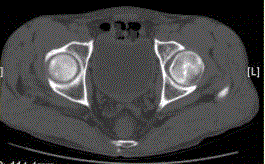

问题 患者男,47岁,左髋部疼痛及压痛6个月,“4”字试验阳性。左髋关节内、外旋活动受限。检查提示:左髋关节活动轻度受限,大腿上部轻压痛。血常规检查正常。髋关节CT及MRI如下图。 对本病例,你首先考虑的诊断是

选项 A.骨髓炎 B.左股骨头缺血性坏死 C.退行性关节病 D.关节结核 E.骨岛 F.左髋关节腔积液

答案 BF